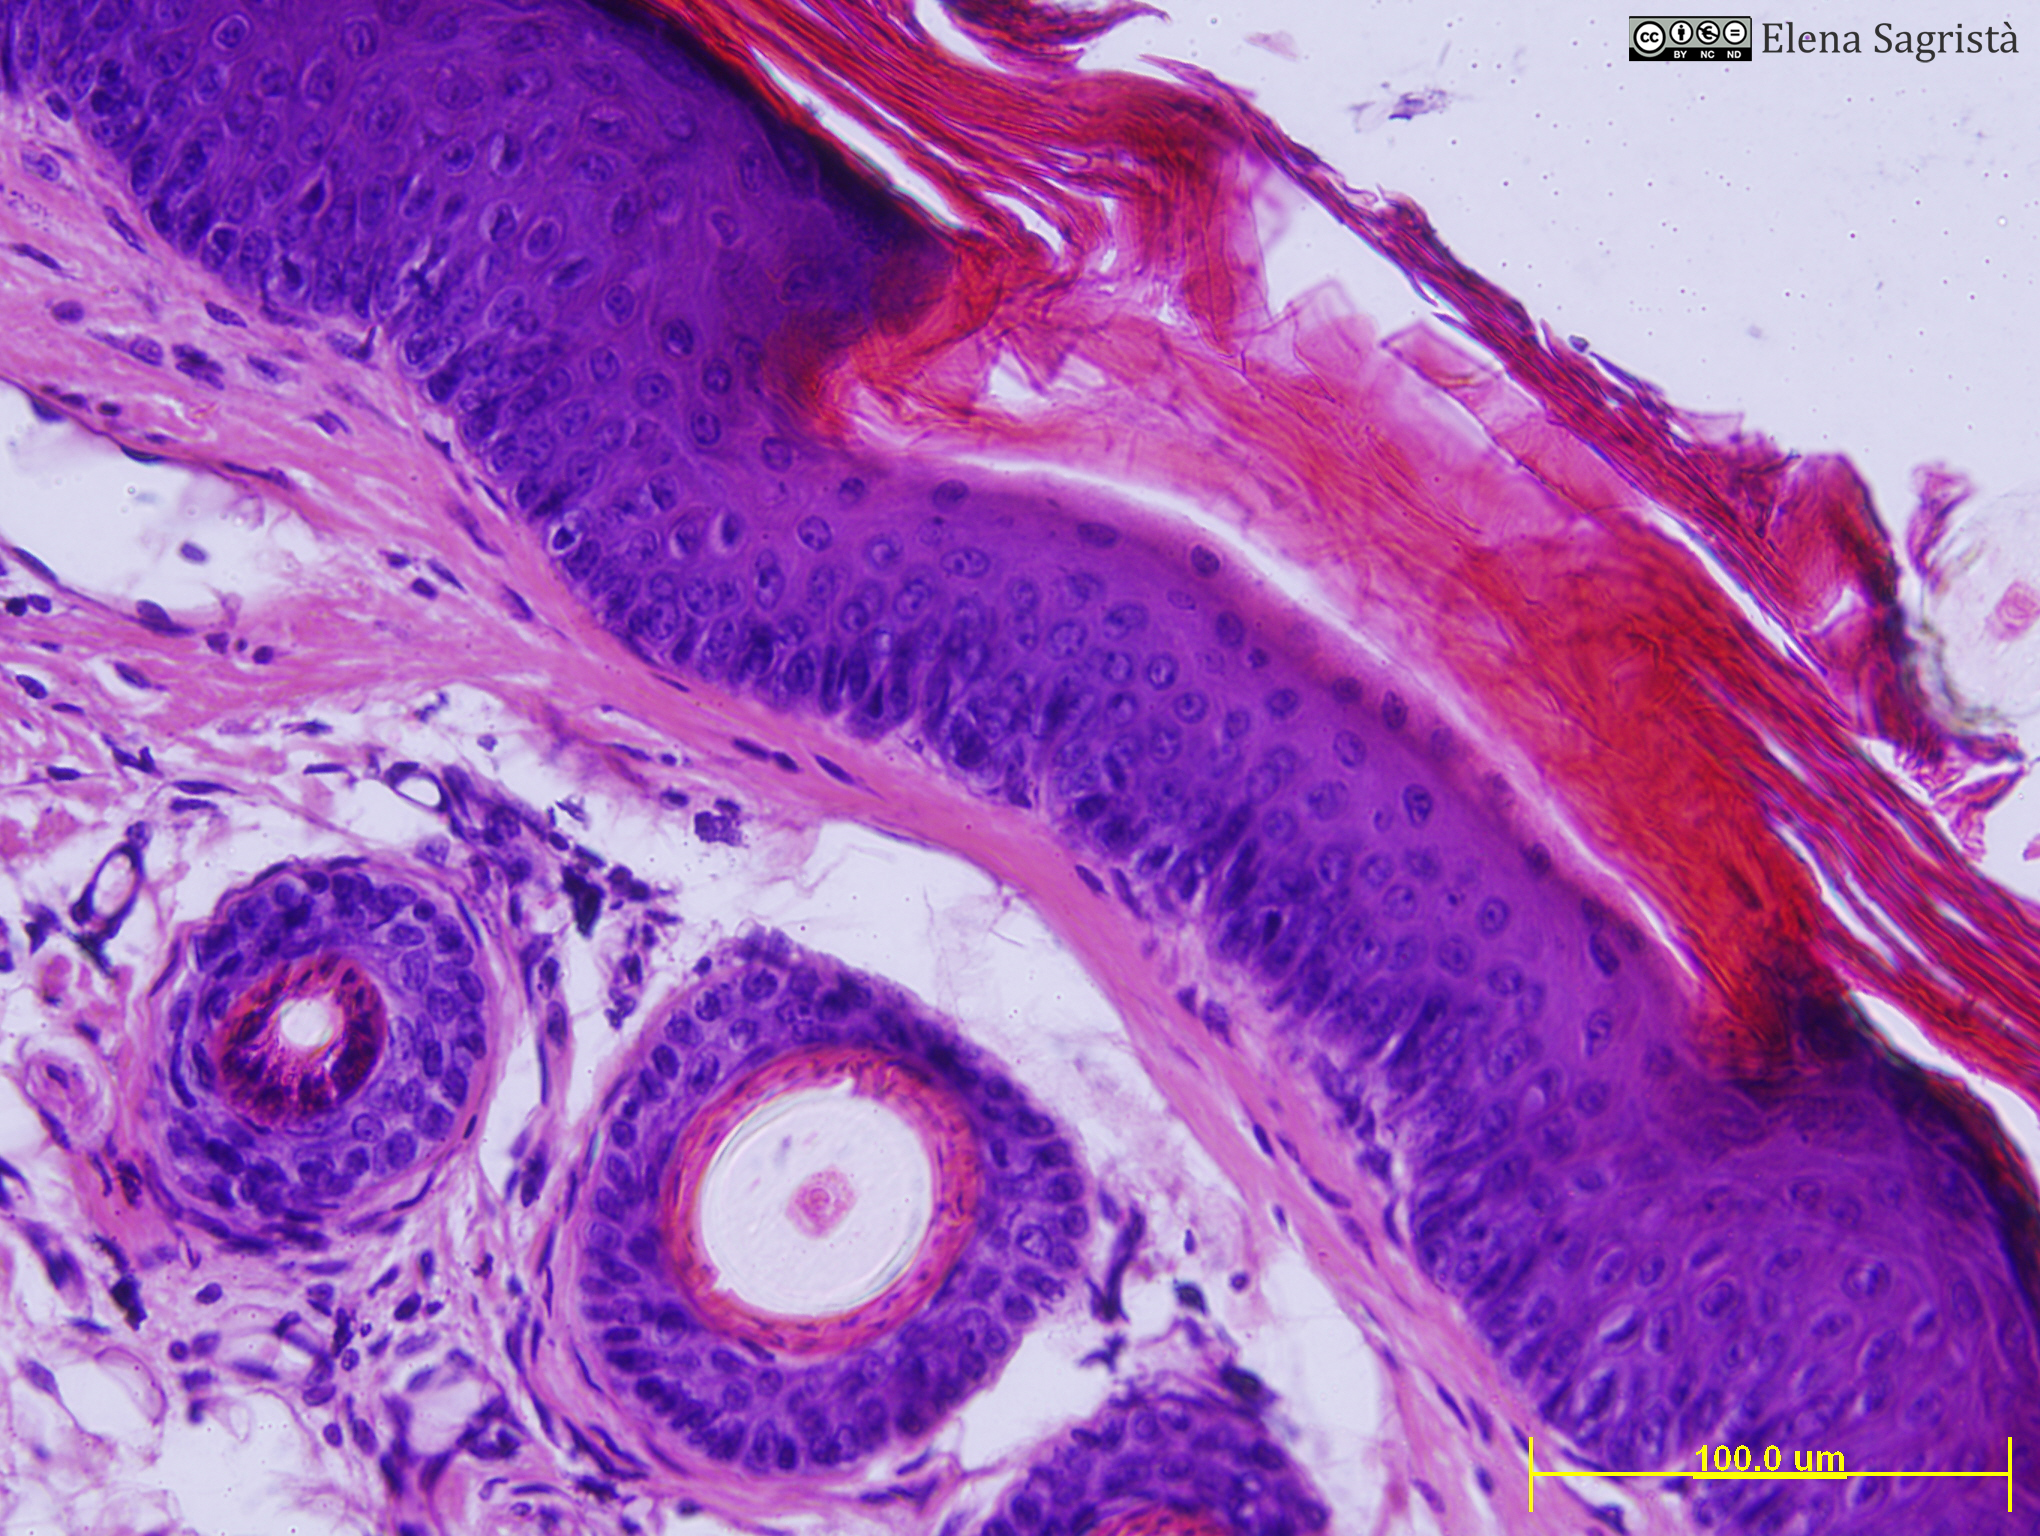

Histologia imatges: 11 Pell

Imatges de preparacions histològiques de Pell. Microscopia òptica.